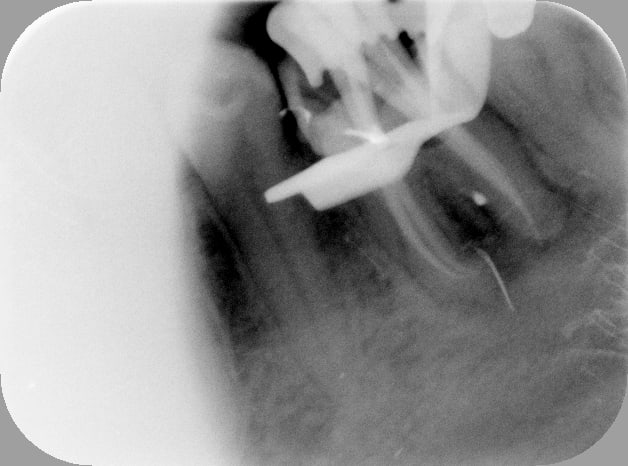

C'est quoi la proba d'avoir une deuxième bio à 5 canaux en 2 semaines?

(la radio excentrée est dégueulasse, mais ça montre les doubles courbures, quelques peu minimisées par l'angulateur...